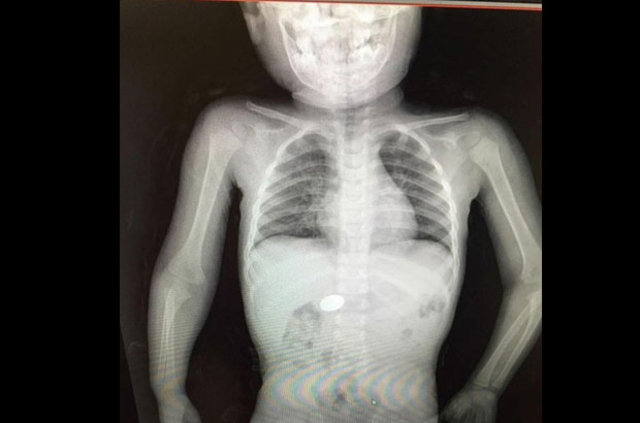

İzmir'deki Tepecik Eğitim ve Araştırma Hastanesi Çocuk Gastroenteroloji Bölümü'nün, yabancı cisim yutan çocukların nefes ve borusu ile midelerinden çıkarttığı, anahtarlık, madeni para, saat pili, ataç, çengelli iğne ve çivi gibi objeler görenleri şaşkına çevirdi.

Çocukların nefes ve borusu ile midelerinden çıkartılan, anahtarlık, madeni para, saat pili, ataç, çengelli iğne ve çivi gibi objeler görenleri şaşkına çevirdi. Anne ve babaların çok dikkatli olması gerektiğini söyleyen Doç. Dr. Maşallah Baran, şöyle dedi:

Genellikle yabancı cisimler 'X' ışınıyla görülebilir. Direk grafi ile metal ve 'X' ışınına duyarlı cisimleri rahatlıkla görebiliyoruz. Ama plastikleri göremiyoruz. Bu durumda oyuncağın bir parçasıyla yutulan parçayı anlamaya çalışıyoruz."

18

Son olarak 9 aylık bir bebek pil yutma şikayetiyle getirildi. Pilin midede olmasına rağmen, yeni olması ve bebeğin yaşının küçük olması nedeniyle 3 saat içinde müdahalemizi yaptık endoskopiyle pili çıkarttık. Buna rağmen midede yanıklar vardı, bir süre hastamızı takip ettikten sonra taburcu ettik." (DHA)